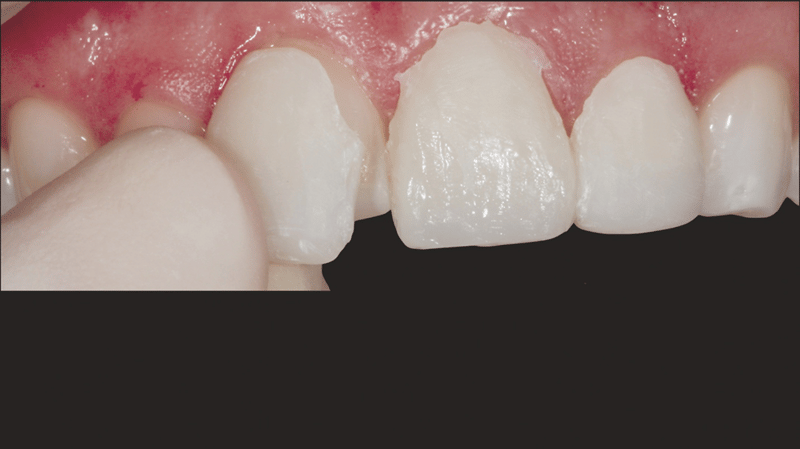

Een jonge vrouw van in de 20, die leed onder de verkleuring van haar bovengebit als gevolg van vroeger trauma, bezocht dr. Jaleena Fischer-Jessop omdat ze weer een mooie glimlach wilde. De patiënte kreeg een conserverende, betaalbare behandeling: directe adhesieve composietveneers zonder preparatie. Dr. Fischer-Jessop koos voor deze methode om de verkleuring te maskeren en de lengte van de bovenelementen aan te passen aan de frontelementen van de onderkaak, waardoor invasievere methoden, zoals implantaten of dure, indirecte veneers, niet nodig waren. De kleuren B1D en Enamel White (EW) werden geselecteerd om het gebit lichter te maken en met de Universal Body-kleur (UB) van Transcend™-composiet werd ervoor gezorgd dat de randen een natuurlijke overgang hadden naar de cervicale gebieden.

- Anamnese: Een vrouwelijke patiënt van in de 20 met een voorgeschiedenis van trauma aan de frontelementen in de bovenkaak. Ondanks het trauma bleven de gebitselementen stabiel, dus implantaten waren niet nodig.

- Esthetische en financiële afwegingen: De patiënte was niet tevreden over het uiterlijk van haar gebit en had het financieel gezien niet breed. Daarom werd gekozen voor directe adhesieve composietveneers zonder preparatie.

Met de ingreep konden de esthetische problemen van de patiënte met succes worden aangepakt; de verkleuring van de frontelementen in de bovenkaak is gemaskeerd en er is nu sprake van een natuurlijk, evenwichtig beeld ten opzichte van de frontelementen in de onderkaak. Het gebruik van directe adhesieve composietveneers zonder preparatie bleek een conserverende, zeer effectieve oplossing te zijn die zowel tegemoetkwam aan de lastige financiële situatie van de patiënte als aan de behoefte aan een minimaal invasieve behandeling.